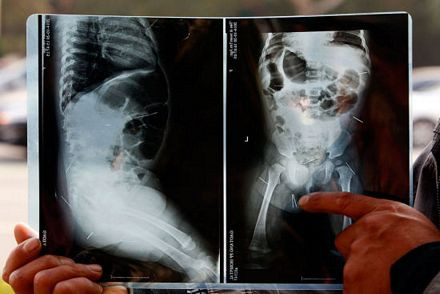

Nhìn vào bức ảnh chụp X-quang, hai vợ kinh hoàng khi thấy 12 chiếc kim nằm ở phần bụng và mông của con gái mới 11 tháng tuổi. Mẹ em bé cho rằng có ai đó đã cố ý đâm kim vào người con gái.

Những chiếc kim bên trong cơ thể bé gái.

Tại bệnh viện, vợ chồng Liu và Fan vô cùng ngạc nhiên khi nhìn thấy các bức ảnh chụp X-quang cho thấy 12 chiếc kim nằm ở phần bụng và mông bé gái.

Bác sĩ Geng, trưởng phòng cấp cứu tại Bệnh viện nhi Bắc Kinh, cho hay vẫn còn 12 chiếc kim trong cơ thể Zixuan, mỗi chiếc kim dài khoảng 1 cm. Bệnh viện sẽ tiến hành một kế hoạch điều trị sau cuộc hội chẩn của các bác sĩ.

Tình trạng của bé gái hiện ổn định, nhưng "những chiếc kim có thể xâm nhập nội tạng khi chúng di chuyển trong cơ thể bé", bác sĩ Geng nói.